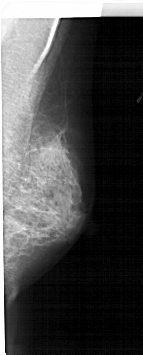

A_1609_1.LEFT_MLO

LEFT_MLO LINES 5191 PIXELS_PER_LINE 2056 BITS_PER_PIXEL 12 RESOLUTION 43.5 OVERLAY

FILE: A_1609_1.LEFT_MLO.OVERLAY

TOTAL_ABNORMALITIES 1

ABNORMALITY 1

LESION_TYPE CALCIFICATION TYPE PLEOMORPHIC DISTRIBUTION CLUSTERED

ASSESSMENT 4

SUBTLETY 2

PATHOLOGY BENIGN

TOTAL_OUTLINES 1

BOUNDARY